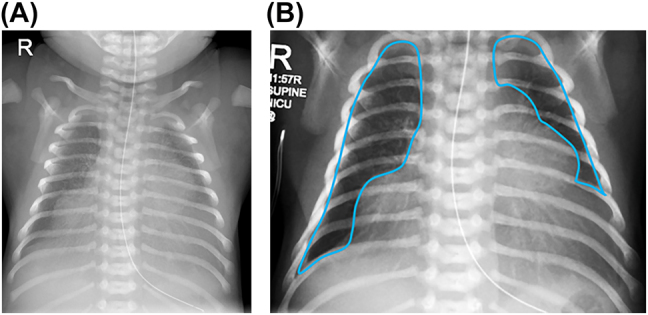

Case presentation: A female infant born at 34 weeks gestation required intubation and ventilation at birth. Chest radiographical imaging revealed bilateral density to the bases of both lung fields with raised hemi-diaphragms. Ultrasound imaging showed focal diaphragmatic eventration with bulging of the dome of the liver into the right and left hemithoraces. Assessment of the electrical activity of the diaphragm during a spontaneous breathing trial demonstrated a mean amplitude consistent with that of ventilated infants of the same gestational age with intact diaphragms. Hence she was extubated which was successful. Chest radiographic thoracic area measured post extubation was 1,654 mm2, equivalent to that of a term infant with severe congenital diaphragmatic hernia. As the electrical activity of the diaphragm was normal this suggests replacement of the diaphragmatic muscle tissue with fibrous bands was likely to be only partial, and hence why extubation was successful. She had other abnormalities presenting in the neonatal period including dermal melancytosis, central hypotonia, hyperinsulinism and poor feeding. The infant underwent extensive investigation which revealed a KMT2D gene mutation associated with Kabuki syndrome.

Conclusions: Physiological pulmonary measurements may add clinical management in bilateratal diaphragmatic eventration.